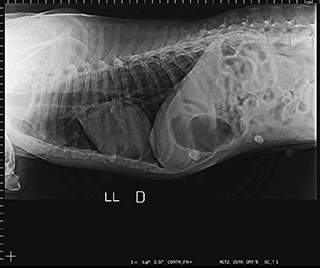

Radiologia Digital Direta / Digital Radiography

As radiografias geradas digitalmente podem ser transmitidas para iPad Apple®, notebooks e smartphones.

iPad com tela Retina Apple® possibilita a visualização das imagens com maior qualidade diagnóstica.

O treinamento aborda a geração das radiografias, a edição digital das imagens, e também a

escolha adequada de técnicas radiográficas como kilovoltagem, corrente elétrica e tempo de exposição.